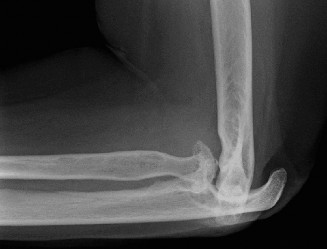

Examination reveals deformity about the elbow with no open lesions or skin tenting. He has a palpable radial and ulnar pulse and is neurologically intact. His images are shown (Figs. 2–85 to 2–88).

Figure 2–85

Figure 2–86

Figure 2–87

Figure 2–88

What is the diagnosis and direction of displacement?

- Monteggia fracture dislocation, posterolateral displacement of the forearm about the humerus

- Simple elbow dislocation, posterolateral displacement of the forearm about the humerus

- Transolecranon complex elbow dislocation

- Simple elbow dislocation, posteromedial displacement of the forearm about the humerus

Discussion

The correct answer is (B). This is the most common type of elbow dislocation, and often does not cause any osseous injury. Posterolateral and posteromedial dislocation account for approximately 90% of dislocations. Adequate pre- and postreduction films are necessary to evaluate for fracture, which would change the classification to a complex injury.